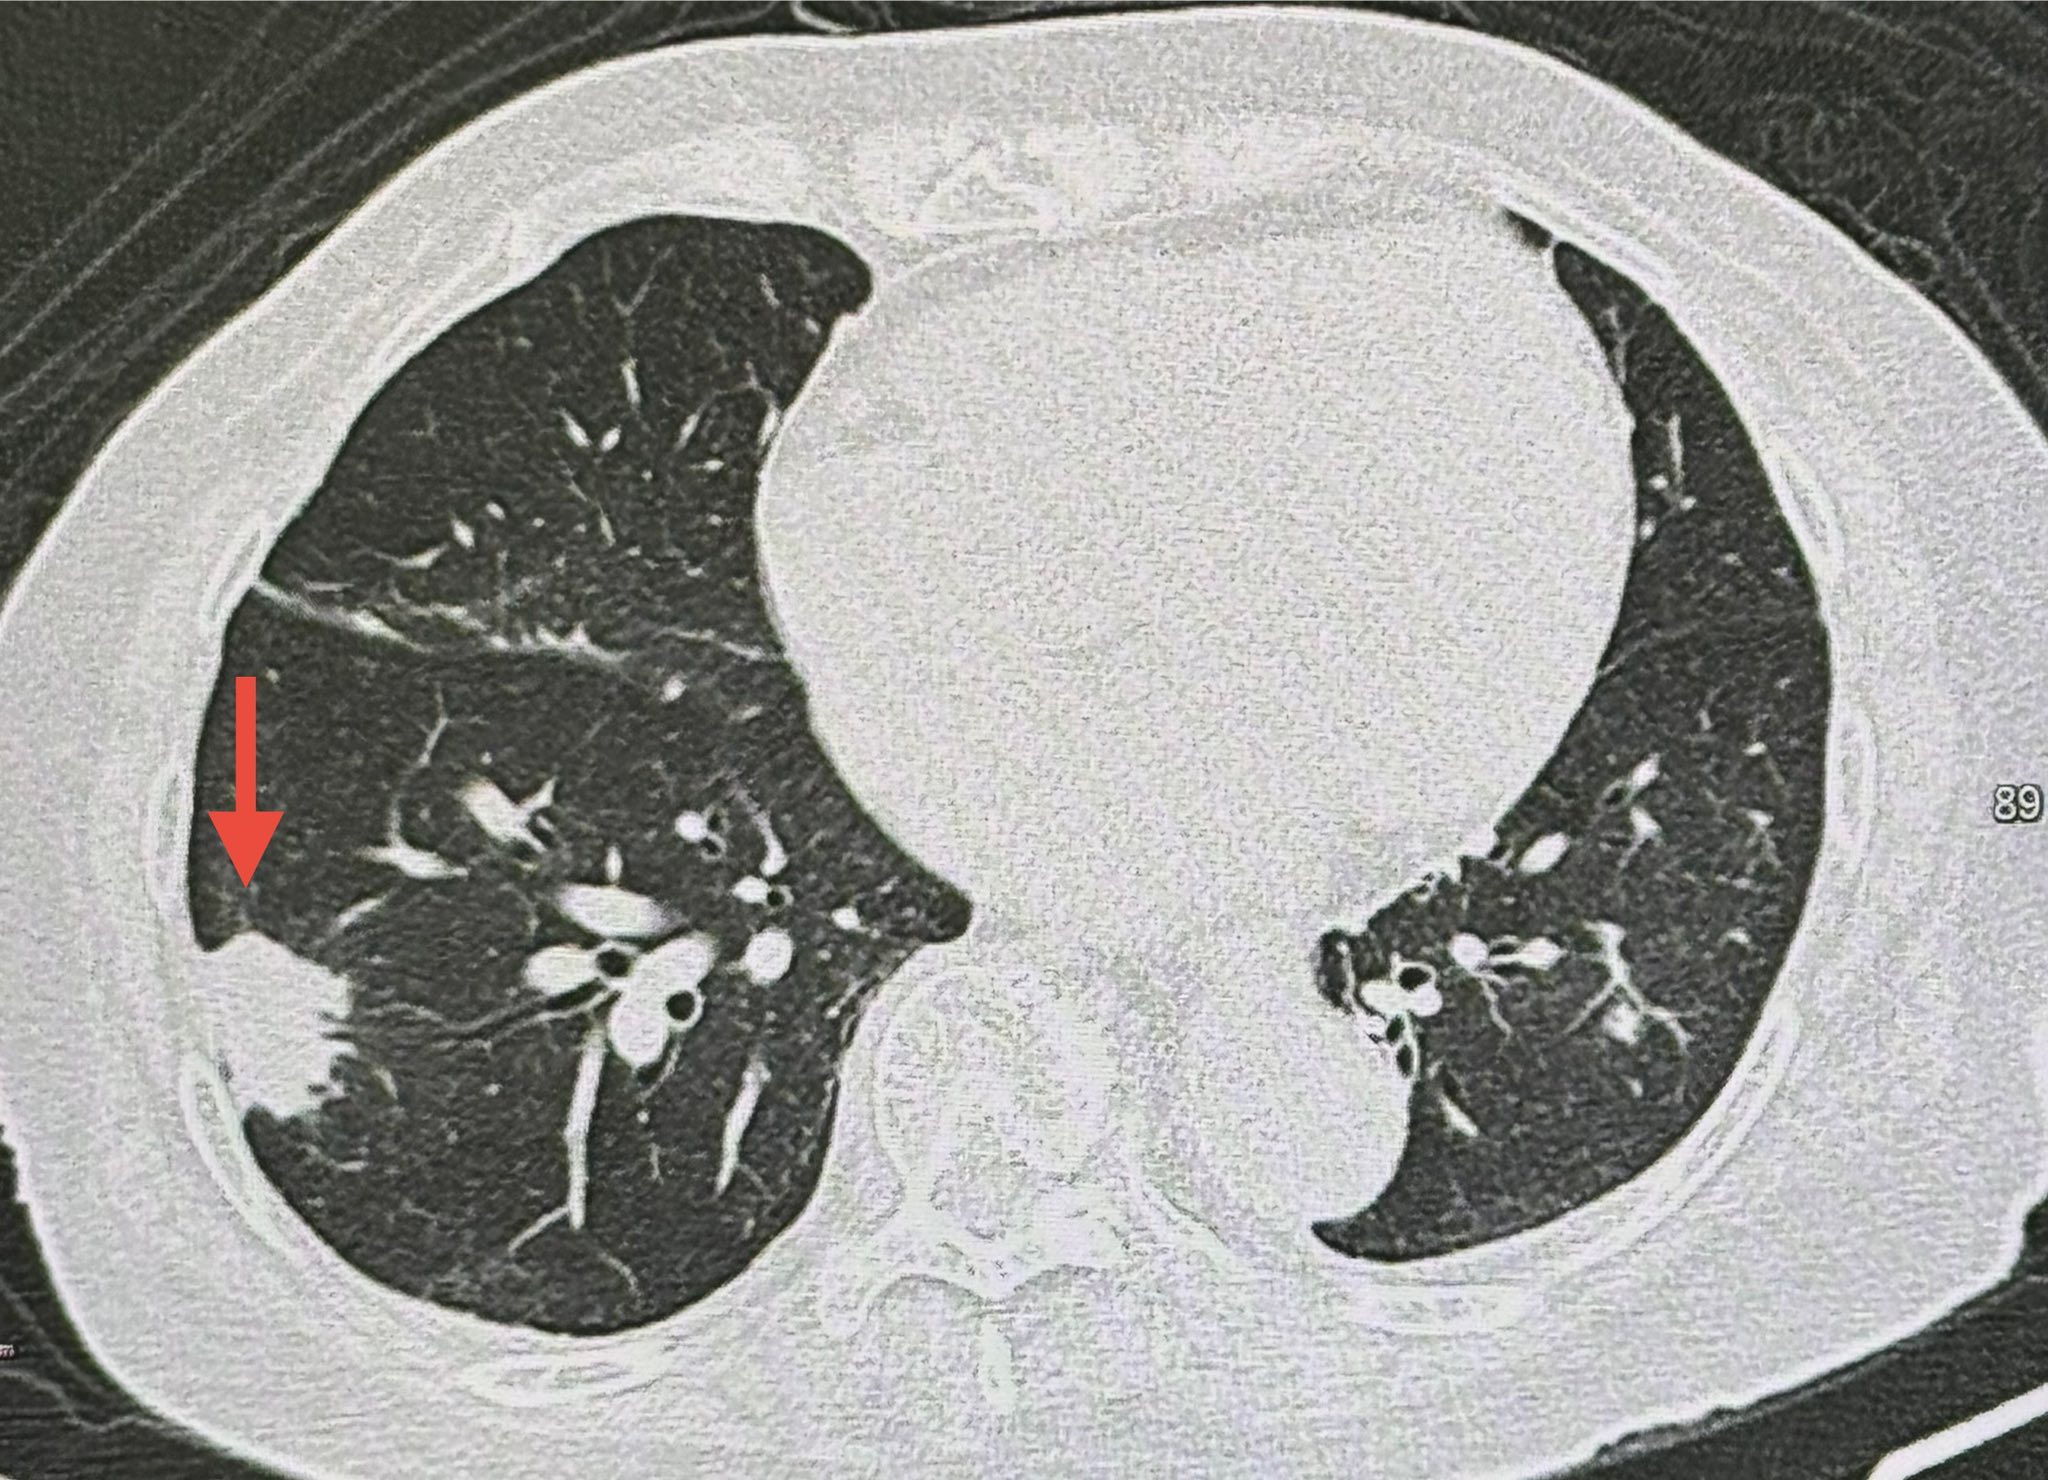

ผู้ป่วยรายนี้เข้ารับการตรวจสุขภาพประจำปี แพทย์ตรวจร่างกายไม่พบไข้ ฟังปอดปกติ แต่การเอกซเรย์ปอดพบเงาผิดปกติบริเวณปอดข้างขวาด้านบน ซึ่งเป็นร่องรอยจากการเคยป่วยวัณโรคในอดีต นอกจากนี้ยังพบก้อนใหม่ขนาด 1.9 x 1.9 เซนติเมตรที่ปอดข้างขวาด้านล่าง ซึ่งไม่เคยพบมาก่อนในปีก่อนหน้า เมื่อทำเอกซเรย์คอมพิวเตอร์ปอด พบว่าก้อนดังกล่าวมีขนาดใหญ่ขึ้นเป็น 3.0 × 2.4 × 2.0 เซนติเมตร

แม้ผลตรวจเลือดค่ามะเร็งทุกชนิดจะอยู่ในเกณฑ์ปกติ แต่แพทย์ตัดสินใจเจาะก้อนด้วยเข็มเพื่อนำชิ้นเนื้อไปตรวจทางพยาธิวิทยา ผลตรวจพบว่าปอดอักเสบจากเชื้อราคริปโตค็อกคัส (Cryptococcus) และเมื่อส่งตรวจเลือดเพื่อหาแอนติเจนของเชื้อคริปโตค็อกคัส พบให้ผลบวกที่ค่าไตเตอร์ 1 : 20